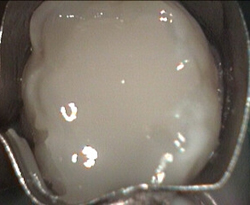

Top of back tooth

Restored